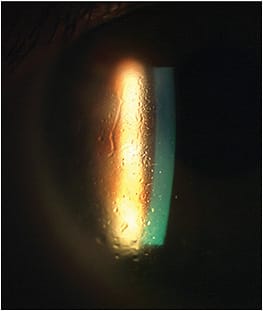

When surface deposits and non-wetting continue to be problematic (Figure 2), an alternative lens material or a different cleaning system may be required.

Debris in Fluid Reservoir Debris accumulation in the post-lens fluid reservoir creates fogging and can occur within minutes or hours of lens wear. When the fogging is significant, patients may be required to remove the lens, clean it, and fill it with fresh nonpreserved saline. As mentioned previously, frequent scleral lens removal may induce inflammation and mucin production, further exacerbating the fogging (Figure 3).